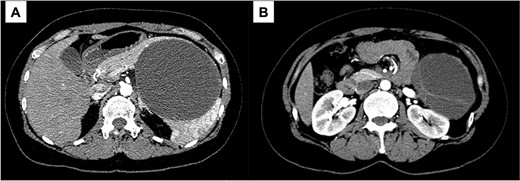

A 43-year-old woman visited our hospital because of abdominal pain. Her medical history was unremarkable and not suggestive of acute pancreatitis or cholelithiasis. Laboratory studies revealed slight anemia and normal levels of amylase and inflammatory markers. Contrast-enhanced computed tomography (CT) showed a multilocular cystic lesion with a septum and a small, hyperdense area suggestive of intratumoral bleeding (Fig. 1). Magnetic resonance imaging (MRI) revealed a multilocular cystic lesion with a thick septum on T2-weighted imaging (Fig. 2). Those findings suggested a pancreatic cystic tumor, including the possibility of MCN, and we decided to perform distal pancreatectomy with splenectomy. A midline incision was made in the upper abdomen. A 15-cm tumor was identified in the tail of the pancreas, displacing the stomach and body of the pancreas. We mobilized the tumor in the tail of the pancreas along with the pancreatic body and spleen en bloc from the retroperitoneum. The tumor was extirpated by dissecting the body of the pancreas (Fig. 3).

T2-weighted MRI; (A) the tumor has a thick fibrous capsule; (B) the tumor has a thick fibrous septum.